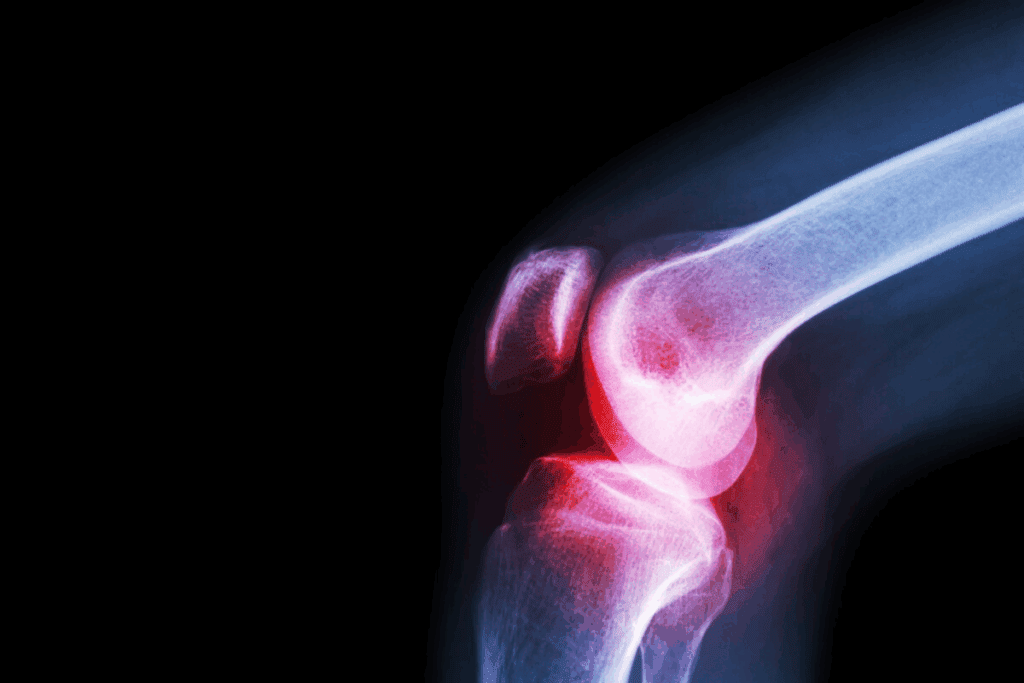

To understand knee dislocation, knowing the knee’s anatomy is key. The knee is a complex joint that links the thigh bone to the shin bone. The kneecap sits at the front, connected to the thigh and shin bones.

The knee is made of three bones: the femur, tibia, and patella. Cartilage covers these bones, reducing friction. Ligaments like the ACL and PCL keep the joint stable.

Muscles, tendons, and ligaments help the knee move and stay strong. Knowing this structure helps us understand dislocations and their effects.

Imaging tests are key to confirming knee subluxation. We use X-rays, MRI, or CT scans to see inside the knee. These tests help us find any ligament tears, fractures, or other injuries.

| Imaging Test | Purpose | Benefits |

| X-rays | Check bone alignment and find fractures | Quick and easy to get |

| MRI | Look at soft tissue injuries, like ligament tears | Great for finding soft tissue damage |

| CT Scans | Give detailed images of bones and soft tissues | Good for complex cases |